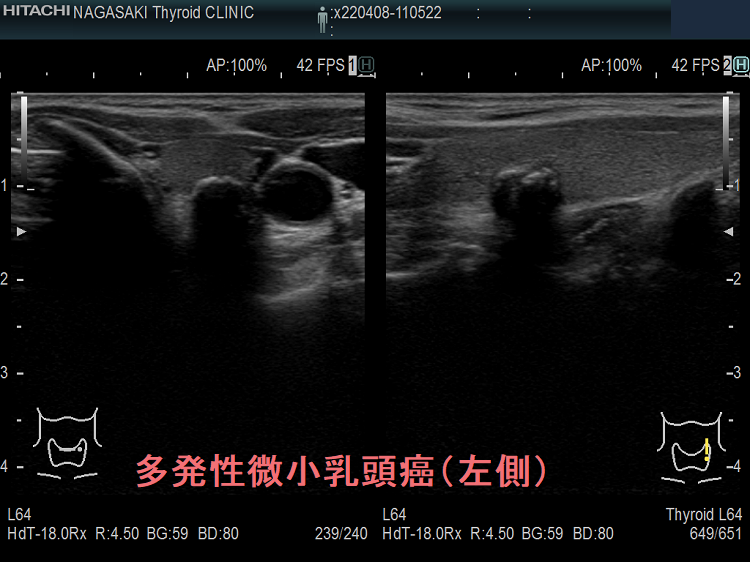

多発性の甲状腺微小乳頭癌

多発性の甲状腺微小乳頭癌は、リンパ節転移しやすいとされます(Am J Surg. 2014 Sep;208(3):412-8.)。

- 海外では、①両葉多発性の場合、②甲状腺癌の家族歴(遺伝性)がある場合、甲状腺微小乳頭癌であっても甲状腺全摘が推奨されます[アメリカ甲状腺学会(American Thyroid Association:ATA)やヨーロッパ分子癌学会(European Society of Molecular Oncology:SMO)のガイドライン](Thyroid. 2016 Jan;26(1):1-133.)(Ann Oncol. 2019 Dec 1;30(12):1856-1883.)(下記)

一方、隈病院の見解では、両葉多発性、甲状腺癌の家族歴(遺伝性)があっても、通常の甲状腺微小乳頭癌と同じ扱いとのです(Eur J Surg Oncol. 2018 Mar;44(3):307-315.)